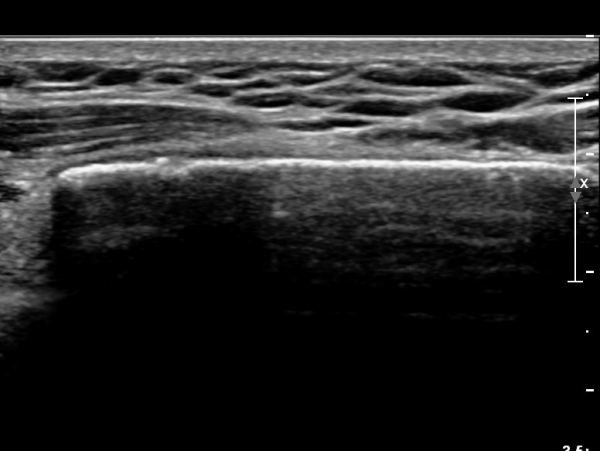

Äá¾Ë»À Á¾´Ü¸é°Ë»ç¿¡¼­ Äá¾Ë »À ±ÙÀ§ºÎÀÇ ÇÇÁú°ñ °ß¿­ÀÌ °üÂûµÊ(»çÁö 4).

ÃÊÀ½ÆÄ°Ë»ç¸¦ ½ÃÇàÇÏ¸é ¹Ì¼¼ÇÑ ¼±»ó°ñÀý¿¡¼­µµ ¿¬ºÎÁ¶Á÷ ºÎÁ¾ ¹× ÇÇÁú°ñ ¿¬°á¼º ¼Ò½ÇÀ» °üÂûÇÒ ¼ö ÀÖ¾î

Èä°øÀÇ ¹Ì¼¼°ñÀý Áø´Ü¿¡ ÃÊÀ½ÆÄ°Ë»ç´Â ¸Å¿ì À¯¿ëÇÏ´Ù.